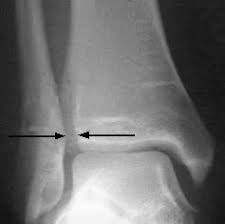

Anterior talofibular ligament injury is the most common of the ligament injuries that can occur as part of the lateral ligament complex injuries 2. In grade 2 anterior talofibular ligament injury, a minor or partial tear can be seen in the ligament. A thorough history including past history and examination Ankle sprains (stretching of the lateral ankle ligaments) are one of the most common injuries to occur in the lower extremity. Anterior drawer testing and mri obtained at initial presentation demonstrated a tear of the anterior talofibular ligament (atfl).

The anterior talofibular ligament (atfl) connects the talus to the fibula and is. Depends from the grade of the torn ligament. Injuries typically occur during plantar flexion and inversion; A grade 2 ankle sprain describes a partial ligament tear, and grade 3 sprains involve complete tearing of one or more ankle ligaments. The most common and significant ligament tears include tears in the anterior talofibular ligament (atfl), calcaneofibular ligament (cfl), and the large deltoid ligament complex. Anterior talofibular ligament injury is the most common of the ligament injuries that can occur as part of the lateral ligament complex injuries 2. Complete tear of the ligament significant tenderness and swelling around the ankle if the doctor pulls or pushes on the ankle joint in certain movements, substantial instability occurs in a grade 2 sprain, some but not all of the ligament fibers are torn. Involves moderate pain and swelling and difficulty walking. Large tear of the atfl. The anterior tibiofibular (atfl), calcaneofibular (cfl) and posterior talofibular (ptfl) ligaments. Ankle sprains (stretching of the lateral ankle ligaments) are one of the most common injuries to occur in the lower extremity. Symptoms include a broader region of point tenderness over the lateral aspect of the ankle, a painful gait or inability to ambulate, bruising and localized swelling due to tearing of the anterior joint capsule, atfl, and surrounding soft tissue structures. This is the ligament that is most commonly sprained with lateral ankle sprains.

Anterior talofibular ligament tear is most commonly seen in sprained ankle with an inversion injury to the ankle, either with or without plantar flexion 1).if associated bony avulsion, it is mostly at the fibular malleolus rather than the talar end of the anterior talofibular ligament with characteristic bright rim sign. The most commonly injured ligament is the anterior talofibular. This is the ligament that is most commonly sprained with lateral ankle sprains. A large number of fibres are torn and there is some instability of the joint. Very difficult to comment when the treatment regimen you received is unknown. The aitfl is the anterior component of the syndesmosis complex (figure 2). This involves a complete tear of the ligament and the joint is completely unstable. A grade 2 sprain describes a partial ligament tear, and grade 3 sprains involve complete tearing of one or more ankle ligaments.